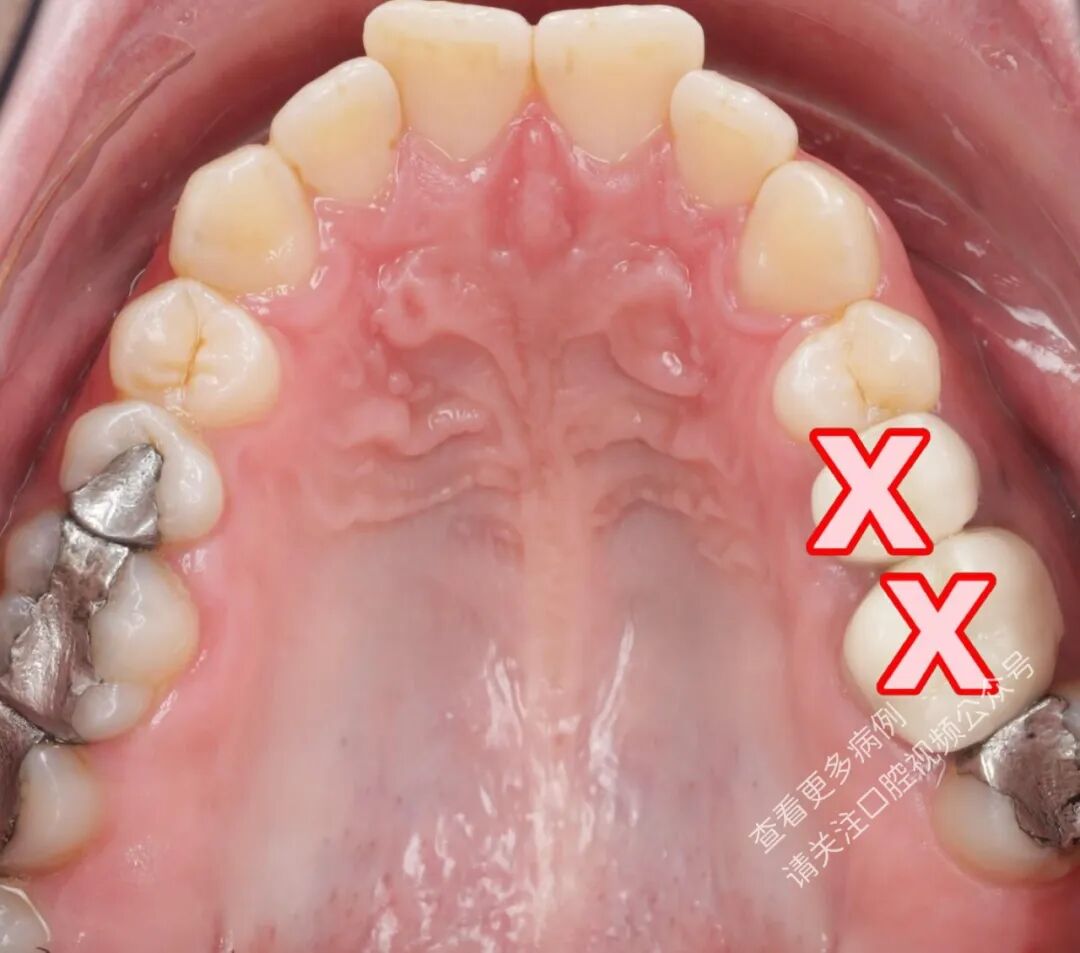

一例同期实施多项正畸操作的典型病例: 从一开始就进行近中移动,并且与扩弓同时进行。

近中移动

零间隙(无间隙状态)